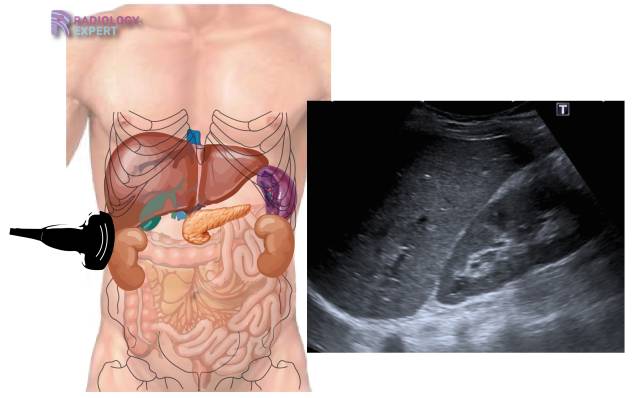

Semarang (usmnews) – Dikutip dari CNNIndonesia Ginjal memiliki peran vital dalam menyaring racun, menyeimbangkan cairan, dan membuang limbah dari darah. Dalam kondisi sehat, urin biasanya berwarna kuning pucat hingga keemasan jernih. Warna ini berasal dari pigmen yang disebut urokrom. Namun, ketika fungsi filtrasi pada unit terkecil ginjal (nefron) terganggu, komposisi dan tampilan visual urin akan berubah secara drastis.

Pengecekan melalui tes laboratorium (urinalisis) dan tes fungsi ginjal (ureum dan kreatinin) adalah langkah medis standar untuk memastikan apakah perubahan warna tersebut merupakan gejala gagal ginjal atau masalah kesehatan lainnya.